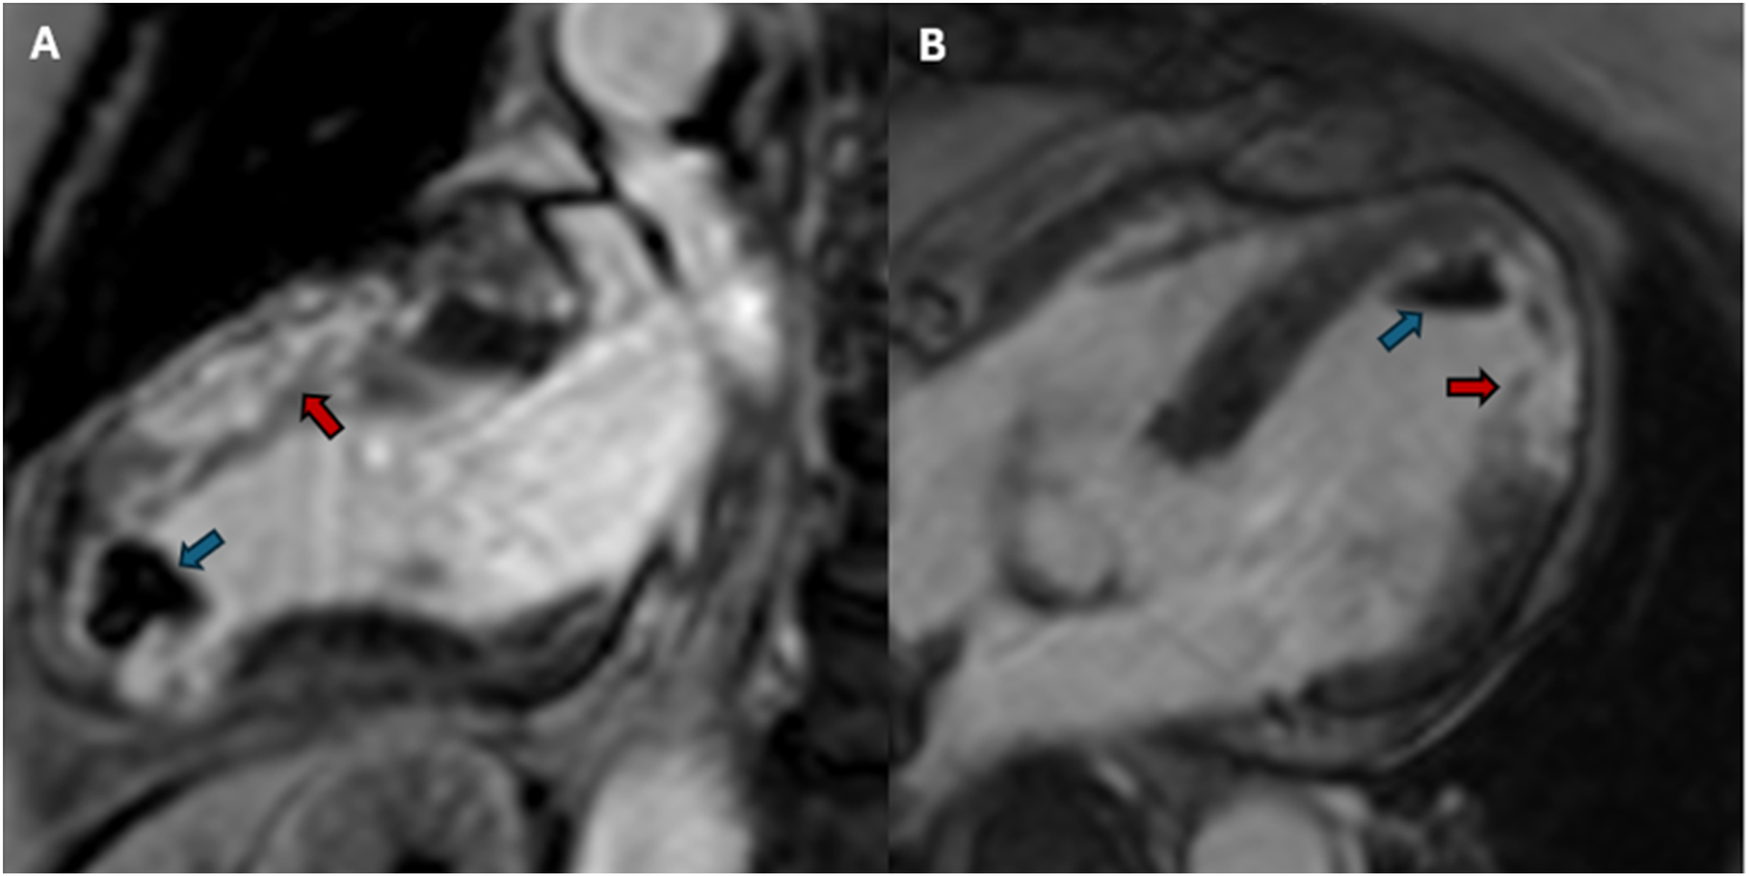

Due to the persistence of epigastric pain, a 12-lead electrocardiogram (ECG) was performed (Figure 1A), showing sinus rhythm at 75 bpm with 1.5 mm ST-segment elevation in leads V5 and V6. Bedside echocardiography showed a mild reduction of left ventricular ejection fraction (LVEF) of 45%, left ventricular apical akinesia, and hypokinesia of the mid-to-distal anterior and anterolateral segments. No significant valvular abnormalities or pericardial effusion were found. A diagnosis of STEMI was made, and the patient received an aspirin loading dose of 250 mg and ticagrelor of 180 mg. Emergency coronary angiography showed a thrombotic sub-occlusion of the left anterior descending artery (LAD) involving the ostium of D1, patency of the previously implanted stent to D1 without restenosis (Figure 2A), and a spontaneous distal embolization defect of the apical LAD with thrombolysis in myocardial infarction (TIMI) 1 flow. Manual thrombus aspiration was performed to the LAD lesion at the level of the bifurcation with D1 only. It was not attempted at the very distal apical LAD because of the small caliber of the vessel. A residual tight stenosis of the LAD at the bifurcation level was treated with a 3.5 × 18 mm DES implantation to the LAD, kissing balloon inflation (3.0/2.0 mm) to LAD-D1, and the final proximal optimization technique with a 3.5 mm NC balloon. Post-procedure echocardiography showed an LVEF of 40%, with akinesia of the apex and of the mid-to-distal anterior and anterolateral segments, without evidence of mechanical complications. Blood examinations showed a peak value of hs-TnI of 19.980 ng/L at 32 h. Continuous ECG monitoring recorded frequent premature ventricular contractions and a brief episode of non-sustained ventricular tachycardia. Therefore, beta-blocker therapy with intravenous metoprolol was started. However, shortly after drug administration, the patient experienced a transient episode of epigastric pain that was responsive to sublingual nitroglycerin. In suspicion of drug-induced vasospasm, metoprolol was promptly discontinued with no symptom recurrence. Heart failure medications including an ace-inhibitor, a mineralocorticoid receptor antagonist, and a sodium-glucose co-transporter 2 inhibitor were started and well-tolerated. On day 3 following the index procedure, cardiac magnetic resonance imaging showed a moderate LVEF reduction (38%), akinesia in the anterior and anterolateral mid-apical regions with apical thrombosis (9 × 20 mm), and late gadolinium enhancement (LGE) extension wall thickness >75% in the same regions with wall motion abnormalities (Figures 3A,B). Rivaroxaban at 20 mg daily was started and ticagrelor was discontinued and de-escalated to clopidogrel, which was continued for 1 week after the index procedure. On day 7, the patient was discharged home asymptomatic on dual antithrombotic therapy with aspirin 100 mg daily plus rivaroxaban 20 mg daily. Discharge ECG showed a reduced R wave progression on the anterior leads with resolution of the ST-segment elevation (Figure 1B). At the 3-month follow-up, the patient was free from angina. She is on dual anti-thrombotic therapy with aspirin and rivaroxaban. A cardiac magnetic resonance found an LVEF of 42%, an unchanged LGE pattern, and a significant reduction in LV apical thrombus size (2 × 8 mm).

Figure 3

Post-PCI cardiac magnetic resonance imaging. (A) Post-PCI cardiac magnetic resonance 2-chamber view. LGE sequences showing an extensive transmural ischemic scar in the anterior wall (red arrow) and a large left ventricular apical thrombus (blue arrow). (B) Post-PCI cardiac magnetic resonance 4-chamber view. LGE sequences showing an extensive transmural ischemic scar in anterolateral wall (red arrow) and a large left ventricular apical thrombus (blue arrow). PCI, percutaneous coronary intervention; LGE, late gadolinium enhancement.